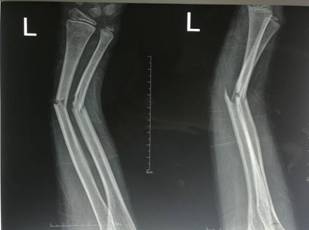

微创治疗肱骨干骨折

优点:闭合复位,不干扰骨折断端,中心固定,利于愈合。

西医手术先进全面:运用DCO理念,阶梯序贯抢救及治疗严重骨盆骨折、多发性、开放性重大骨折创伤;常规开展复杂骨盆髋臼骨折、手足显微外科的手术治疗;以最先进的生物学固定理念为指导,运用微创手术技术治疗骨折,包括:四肢长骨骨折的交锁髓内固定技术、MIPPO(微创经皮钢板内固定技术)、股骨近端骨折髓内固定技术(PFNA)、外固定支架固定技术等等均达国内先进水平。